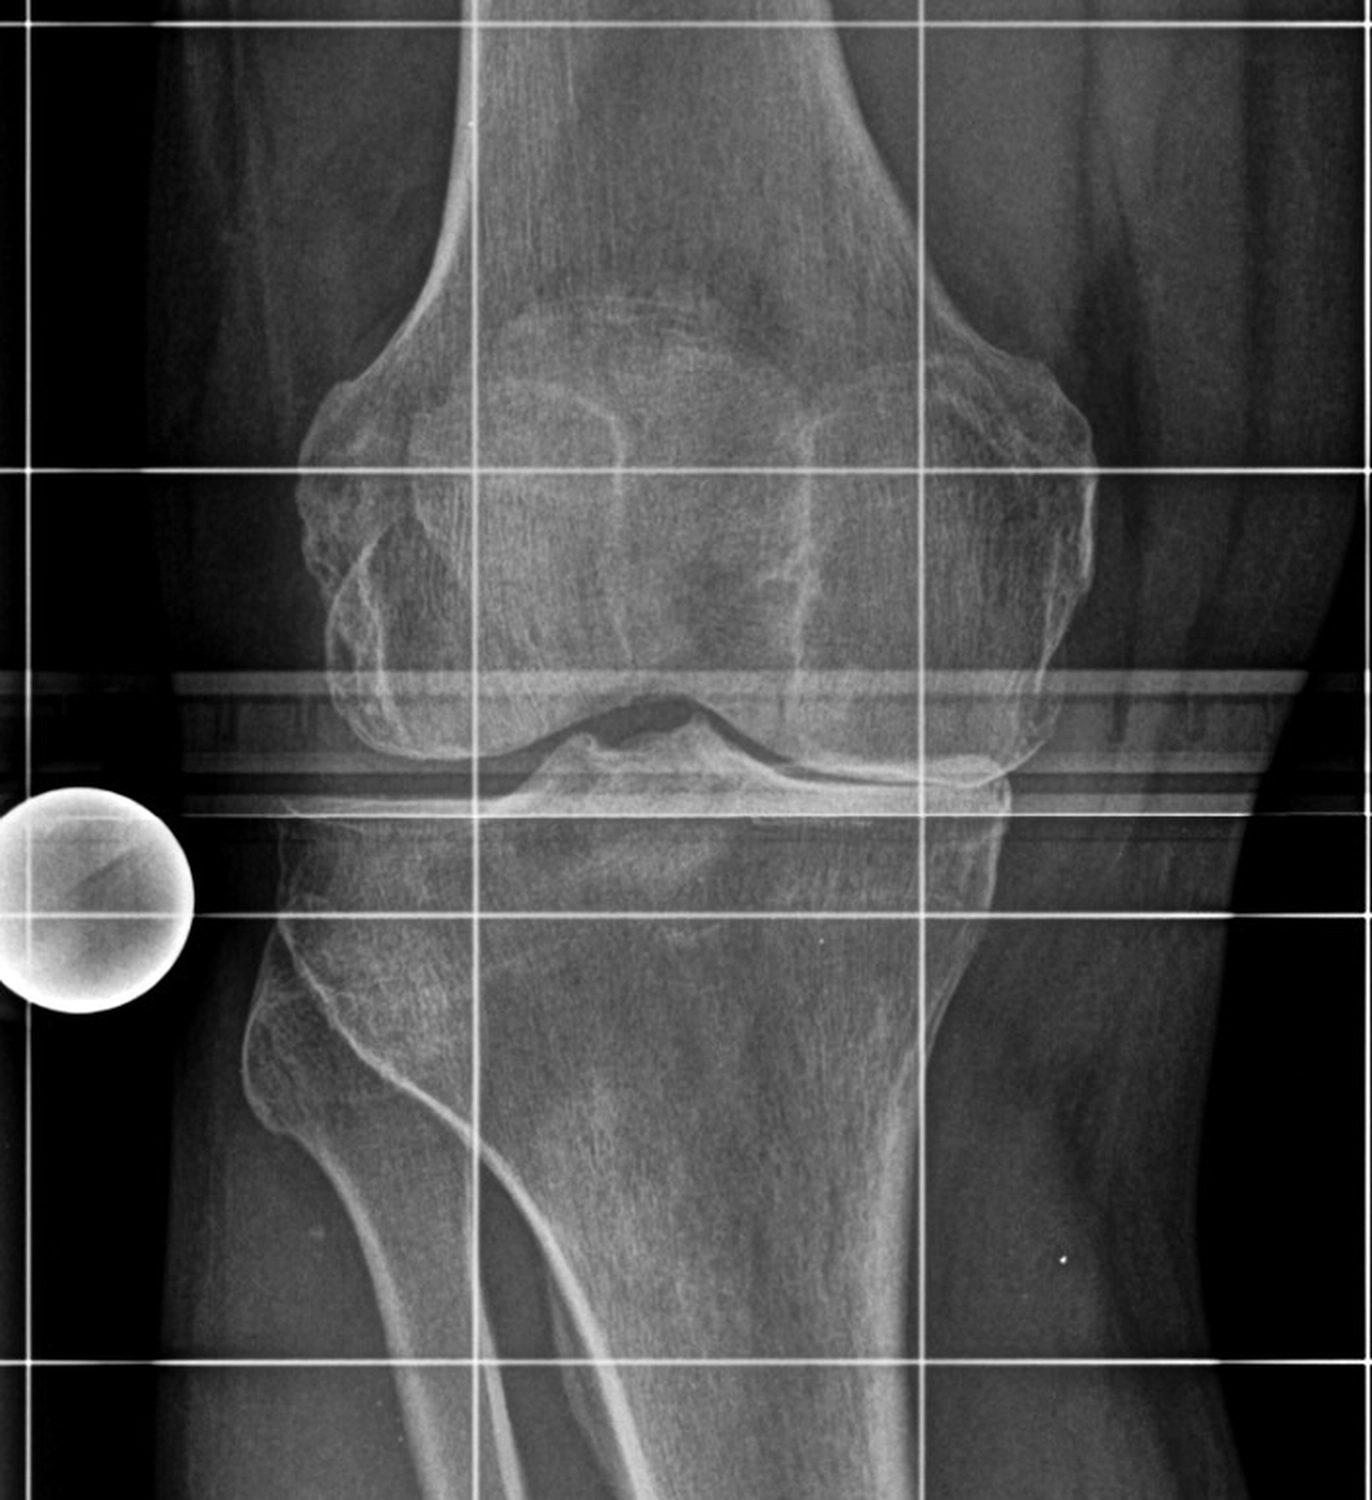

Das Kniegelenk ist das größte und eines der am stärksten belasteten Gelenke des menschlichen Körpers. Bei jeder Bewegung – Gehen, Treppensteigen, Hocken oder Stehen – wirken erhebliche Kräfte auf die Gelenkflächen von Oberschenkelknochen (Femur), Schienbein (Tibia) und Kniescheibe (Patella).

Diese Flächen sind von einer glatten Knorpelschicht überzogen, die wie ein Stoßdämpfer wirkt und ein reibungsloses Gleiten ermöglicht. Im Verlauf des Lebens kann sich dieser Knorpel jedoch abnutzen oder geschädigt werden – man spricht dann von einer Arthrose.

Die Kniegelenksarthrose (Gonarthrose) kann viele Ursachen haben. Häufig sind mehrere Faktoren beteiligt, die sich gegenseitig verstärken.